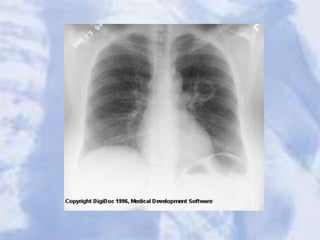

LUL Atelectasis: Loss of heart borders/silhouetting. Notice

over inflation on unaffected lung